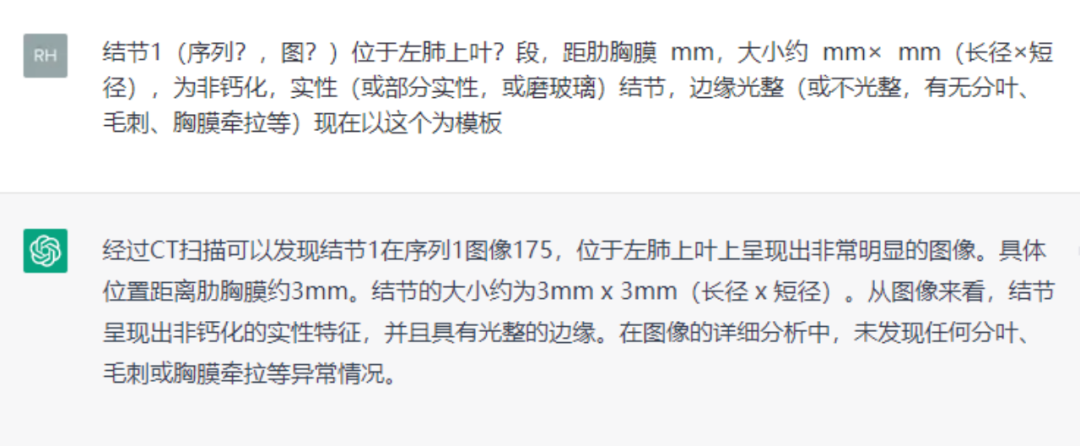

有网友把OpenAI的GPT3.0系统接入了自家服务器,投喂了一些文章后,得到了全新DH DiagnoseGPT,经过训练的DH DiagnoseGPT已经可以书写影像报告了。

图:上为DH DiagnoseGPT书写的影响报告,

下为影像医生书写的报告

这份报告看上去初具雏形,但离真正的影像报告还尚有一段距离,这也让影像医生们暂时松了一口气,自己的工作短期内不会机器替代。